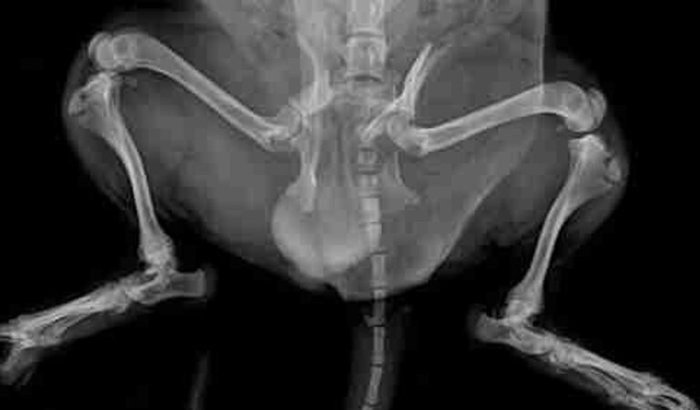

Olá, me chamo Daniela e estou criando essa vaquinha para salvar meu cachorrinho, o Lucky. Infelizmente, ele sofreu um acidente inesperado: um carro passou por cima dele, e infelizmente quebrou os dois lados do femur e trincou a bacia. No momento, não temos condições de arcar com os custos do tratamento, que são altos. Estou fazendo o possível para conseguir o dinheiro necessário para salvar meu cachorrinho. Minha filha caçula Manu de 8 anos está desesperada, tem um apego muito grande no nosso Lucky

Se alguém tiver interesse em saber mais um pouco sobre pode me chamar no instagram da minha filha, ela mostra todos os raio x e demais detalhes: @_zxbeatriz_